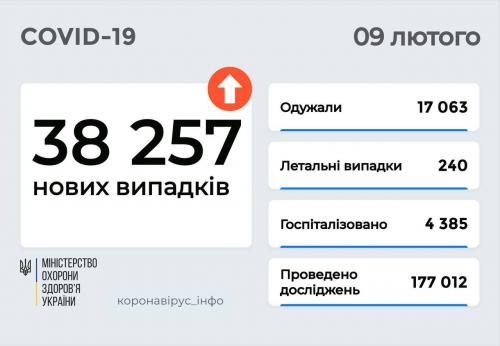

МОЗ: Уперше з початку пандемії було зроблено понад 100 тисяч ПЛР-досліджень за добу